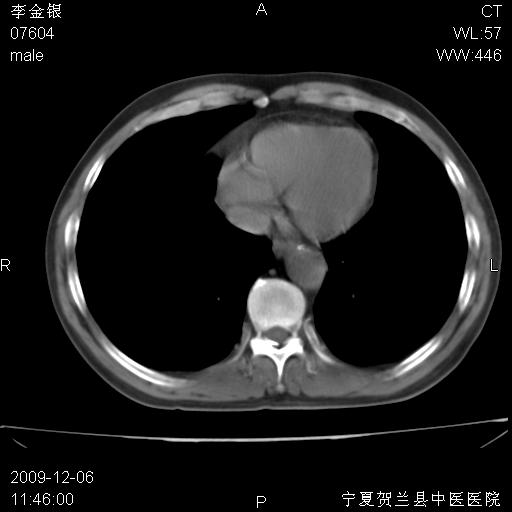

该病人 ,男,62岁,主因咳痰带血两天

考虑右肺中央型占位性病变并阻塞性肺炎.(右肺上叶支气管变窄),建议支纤镜检查.

考虑右肺中心型肺癌伴阻塞性肺炎及右肺门淋巴结转移,建议纤维支气管镜进一步检查。

支气管壁明显增厚 管腔狭窄,腔静脉后多个淋巴肿大,结合年龄病史考虑右肺上叶中央型肺癌并阻塞性肺炎

右肺上叶后段支气管阻塞,右上肺门占位,相应肺段阻塞性肺炎,右肺门有淋巴结肿大。诊断右肺上叶中心型肺癌,阻塞性肺肺炎、右肺门淋巴结转移。

右上叶支气管狭窄,管壁增厚,远端斑片状软组织影,病灶邻近叶间裂,叶间裂无移位。

诊断右肺中央型肺癌。

那个片影应该大部分都是病灶,病灶沿肺段支气管分支生长,后段完全显示不清、闭塞。若为不张应该伴有叶裂的移位,若为炎症应有空气支气管征。

右肺中心型肺癌伴阻塞性肺炎及右肺门与纵膈淋巴结转移很典型,可纤维支气管镜进一步检查

考虑右侧中央型肺癌伴右肺上叶后段阻塞性炎症、肺不张、右肺门和纵隔淋巴结肿大。

右肺上叶中心型肺癌,阻塞性肺炎、右肺门和纵隔淋巴结转移。